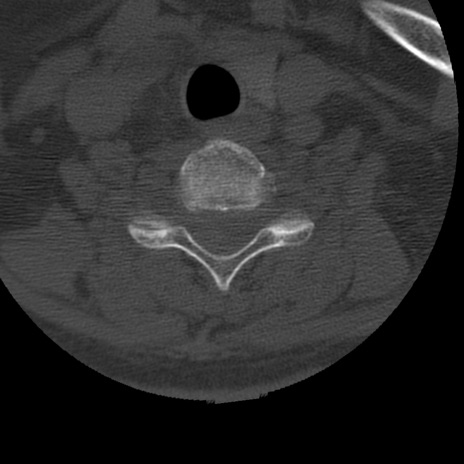

症例50 頚椎CT(横断像)

頚椎CT